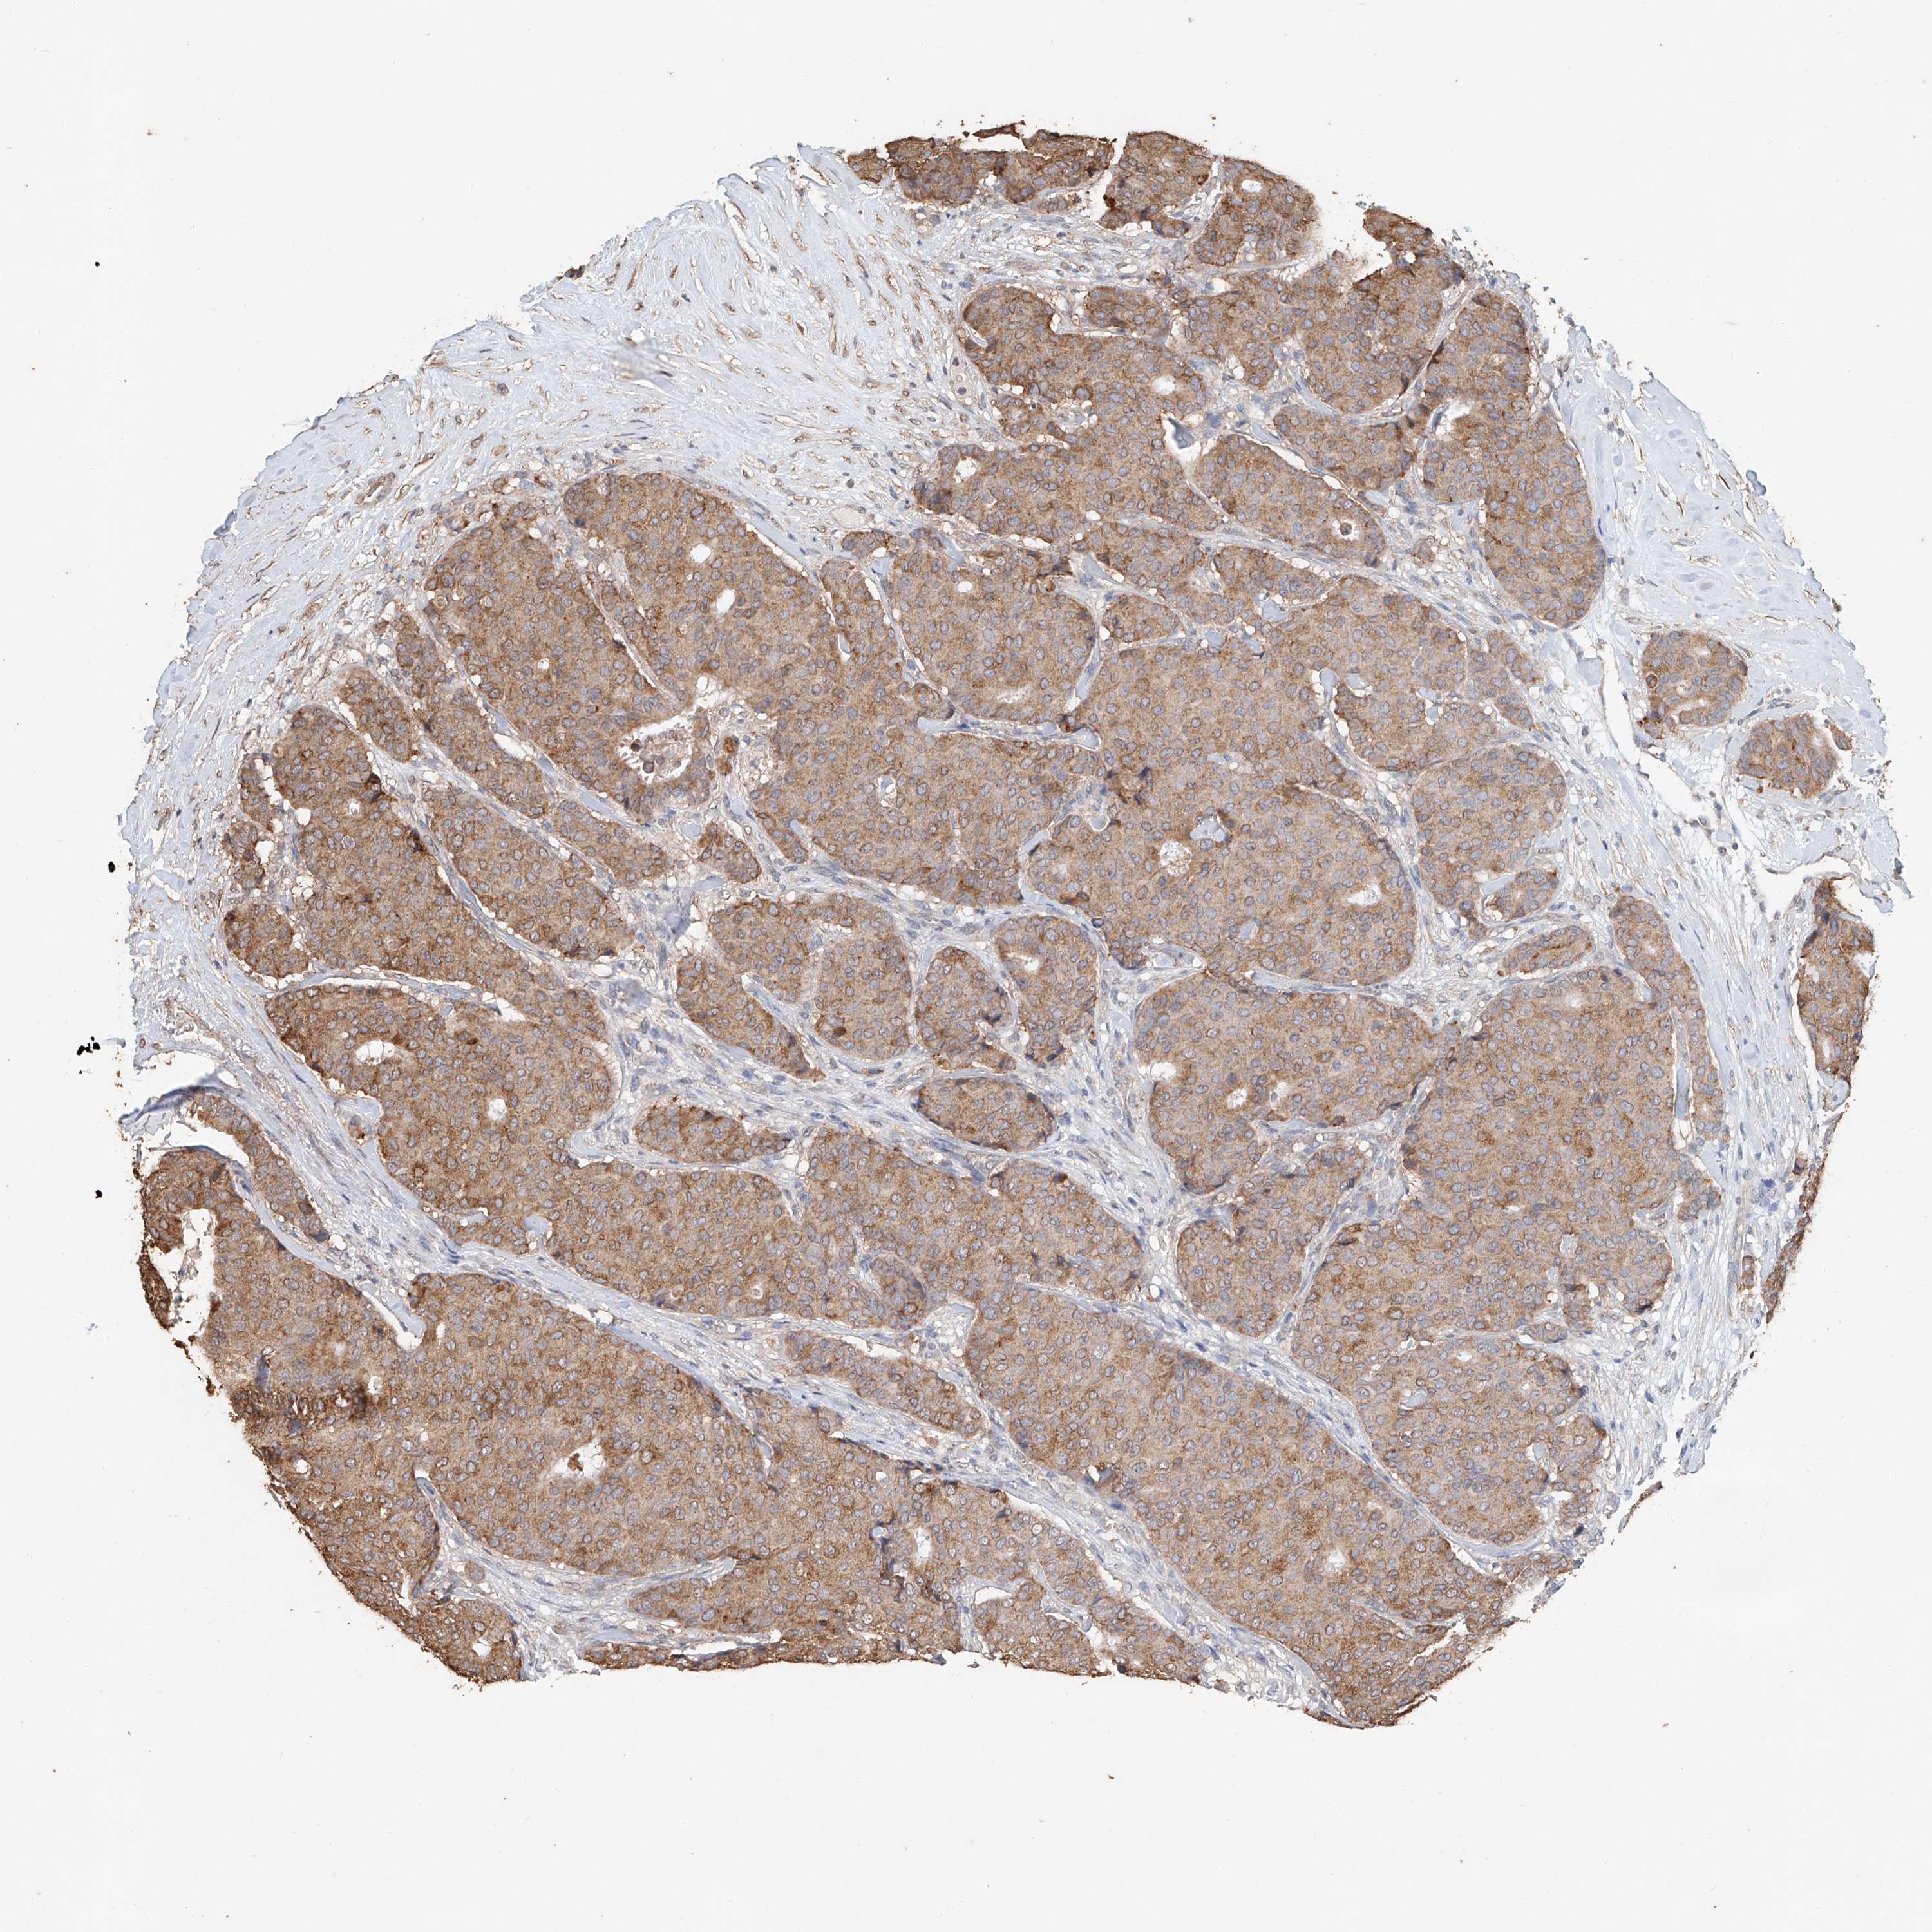

CANCER BREAST CANCER Show tissue menu

BRCA TCGA BRCA VALIDATION PROTEIN EXPRESSION